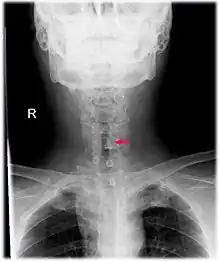

| Neck AP x-ray of patient with post-intubation subglottic stenosis, as shown by the narrowing in the tracheal lumen marked by the arrow. | |